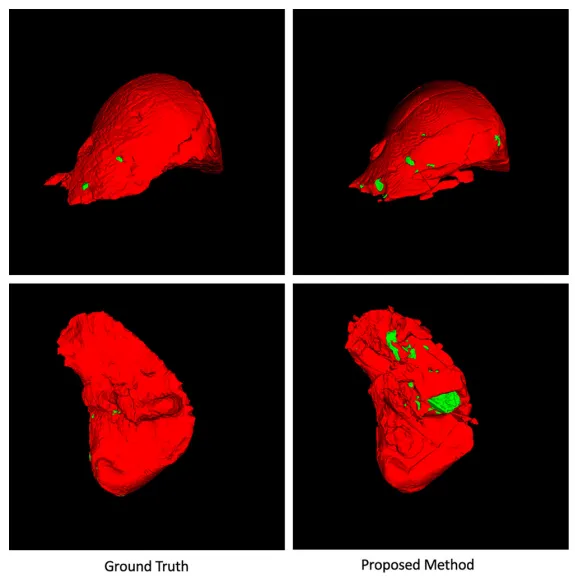

三维重建结果的对比验证了方法在体积空间中的连续性保持能力。左侧金标准与右侧预测结果的高度吻合,不仅体现在整体形状的准确性上,更表现在细小结构的完整保留方面。肿瘤结节的空间定位精确,体积计算与真实值高度一致,这为术前规划和定量评估提供了可靠的三维数据基础(图4)。

图4.所提方法与真实体数据的3D重建结果的可视化对比